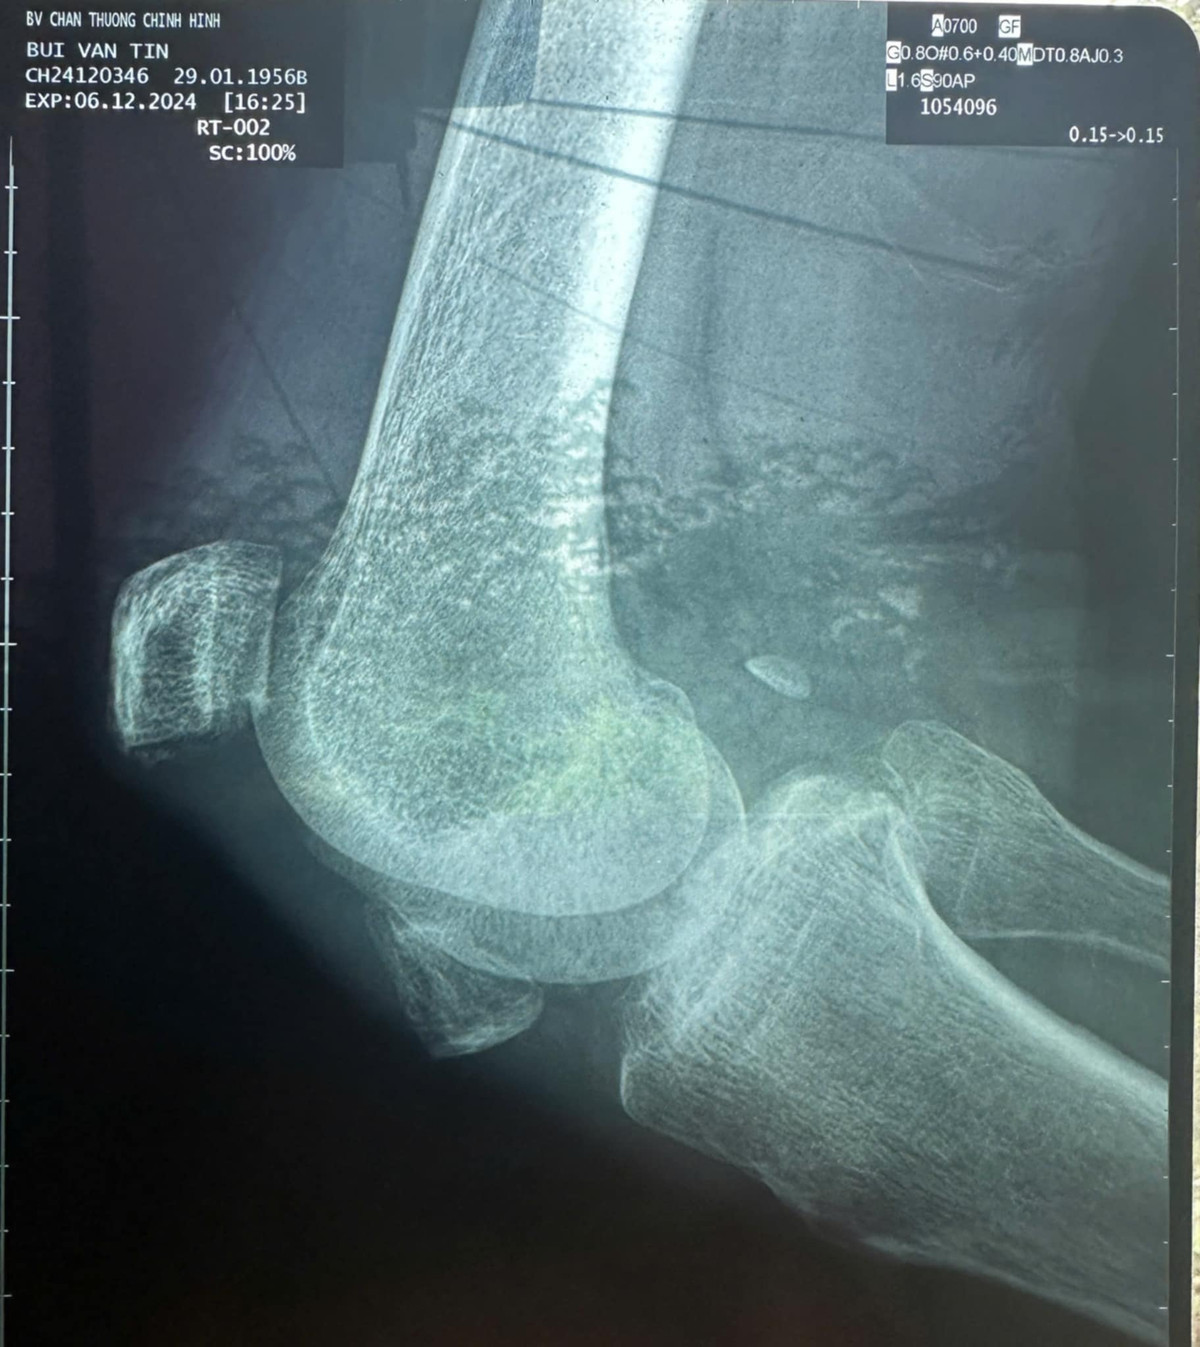

Theo nhạc sĩ Tô Hiếu, diễn viên Thương Tín đã đi khám chữa bệnh vào ngày 6/12 tại Bệnh viện Chấn thương Chỉnh hình TPHCM. Theo đó, chân phải của nam diễn viên bị vỡ đôi bánh chè khớp gối. Bác sĩ nói không thể hồi phục lại được nữa.

Thương Tín đi khám chân tại Bệnh viện Chấn thương Chỉnh hình TP HCM. Ảnh: Tô Hiếu

Chân trái của Thương Tín bị viêm khớp gối nặng, phải uống thuốc điều trị lâu dài. Bác sĩ cho biết hiện tại diễn viên Thương Tín rất yếu, khi nào sức khoẻ bảo đảm mới có thể tiến hành mổ lấy 2 miếng bánh chè ra. Bác sĩ lưu ý diễn viên Thương Tín hạn chế đi lại, nên đi xe lăn.

Tình trạng chân của diễn viên Thương Tín. Ảnh: Tô Hiếu